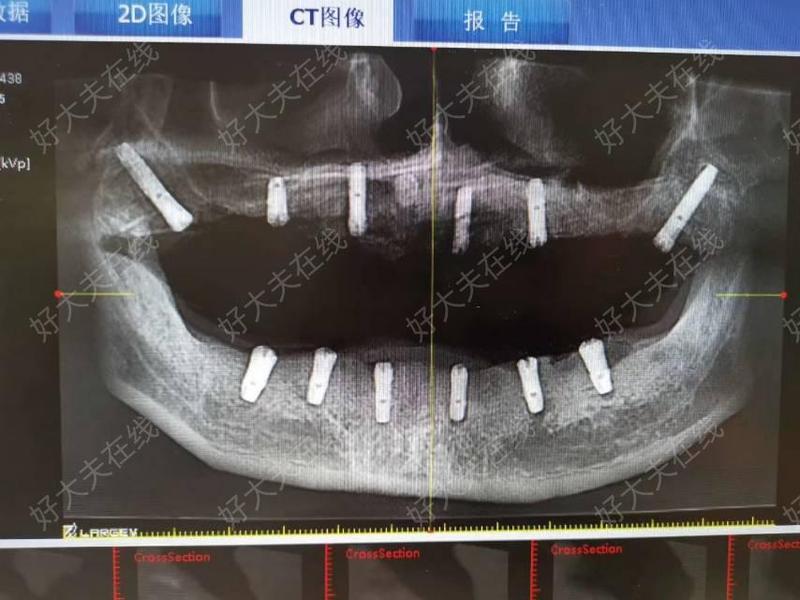

3、北京治療經歷 在北大口腔醫院,我接受了全面的檢查,包括抽血CT螺旋以及全身骨掃描等安金剛醫生根據我的檢查結果,為我制定了靜脈輸液帕米膦酸二鈉的治療方案這一方案是安醫生團隊經過三年研究得出的,已經成功治療了幾百名頜骨骨髓炎患者經過連續三天的輸液治療,我明顯感覺到腫脹部位在逐漸消退;神經內科與康復科聯合診療部分醫院設有神經修復中心,結合神經內科藥物如營養神經藥物康復科物理治療如電刺激感覺訓練及中醫針灸需選擇有神經修復經驗的針灸師,可能對慢性損傷有效二推薦醫院國內綜合醫院神經外科口腔頜面外科北京北京大學口腔醫院口腔頜面外科北京天壇醫院功能;醫院拍牙片的價格一般在幾十元到幾百元不等,具體受以下因素影響1醫院級別不同級別醫院的收費標準存在差異大型綜合醫院因設備先進技術規范,價格通常較高社區醫院或??瓶谇辉\所可能相對較低例如,三甲醫院的牙片費用可能比二級醫院高出30%50%2牙片類型醫院提供的牙片類型多樣,價格因技術;費用明細CT檢查費170元,掛號費7元,單次總費用177元因需對比數據或復查,共進行2次CT,總費用354元目的確定種植區域骨量是否充足,規劃種植體型號及植入角度下午口腔醫院補充CT檢查項目重復CT掃描可能因中心醫院CT設備精度不足或口腔醫院需獨立評估,需再次檢查掛號費未明確具體金額。

4、三在北京大學口腔醫院的治療 檢查與確診安主任安排了全景片頜面部CT平掃和骨掃描等檢查,等待結果大約需要1周時間結果出來后,確診為下頜骨骨髓炎治療方案安主任安排了住院治療,輸了3天特定的液體用于治療癌癥骨轉移的藥物,但經安主任團隊研究發現對下頜骨骨髓炎有良好效果輸液期間;2 普通口腔X光機價格通常在2000元區間例如藍野牙片機約2300元,廣東佛山精拓器械店的配傳感器高清一體成像拍片機約83286元3 高端全景機及CT設備這類多功能設備價格顯著上升,基礎全景機如韓國登騰約25萬元,而大型醫療級設備如武漢大學口腔醫院采購的NewTom VGi口腔CT單價達15988萬元選擇時需根據臨床需求平衡功能與預算,便攜設備滿足基礎診斷,全景CT;特殊器械若需使用顯微根管治療設備或CBCT錐形束CT輔助診斷,費用可能額外增加5001000元顯微技術能精準定位隱匿根管,提高治療成功率地區差異對價格的影響一線城市北京上海等地的三甲醫院或高端私立診所,單根管治療費用普遍在15003000元例如,北京大學口腔醫院根管治療收費標準顯示,前牙單;在正規的三甲醫院口腔科進行口腔CT的拍攝,費用大概在450元左右CT可以直觀的,看出炎癥的位置,以及炎癥的擴散面積和牙齒的立體結構,能夠徹底的看清楚炎癥的位置,是理想治療牙齒的拍攝方式,也是大多數正規醫院的口腔科,所采取的術前片術中片和術后片的方式,口腔CT對而患者的牙齒顯示度較好,通常。